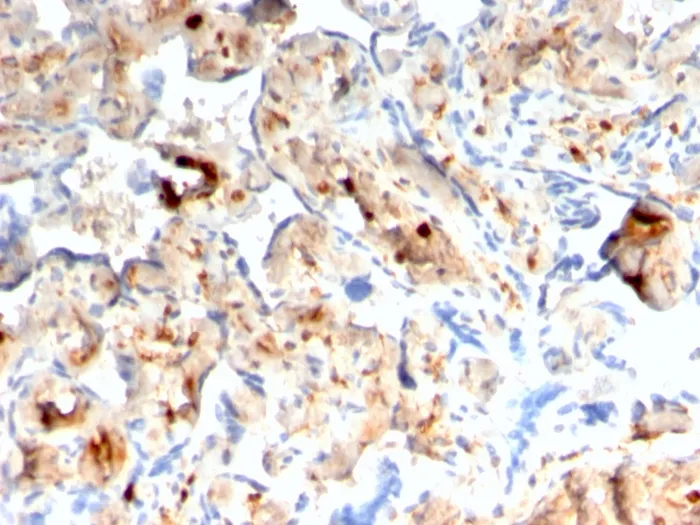

Anti-S100A4 / Metastasin / Calvasculin (Marker of Tumor Metastasis)(rS100A4/1481), CF568 conjugate

S100A4 belongs to the S100 super-family of proteins containing 2 EF-hand calcium-binding domains. S100 genes include at least 25 members, including S100A1-S100A18, trichohyalin, filaggrin, repetin, S100P, and S100Z. S100A4 exerts its function via direct interaction with a number of proteins including P53, P63, non-muscle myosin IIA, 64 integrin, and liprin b1. S100A4 is overexpressed in highly metastatic cancers, which makes it useful as a marker of tumor progression. Primary antibodies are available purified, or with a selection of fluorescent CF® Dyes and other labels. CF® Dyes offer exceptional brightness and photostability. Note: Conjugates of blue fluorescent dyes like CF®405S and CF®405M are not recommended for detecting low abundance targets, because blue dyes have lower fluorescence and can give higher non-specific background than other dye colors.Synonyms:

Flow, intracellular (verified) | IF (verified) | IHC, FFPE (verified) | WB (verified)Validated Applications:

FC, IF, IHC, FFPE, WBPositive Control:

HeLa, A549 or A375 cells (IF/FACS). HeLa, A549, T98G or A375 cell lysate (WB). Human placenta tissue (IHC).Concentration: